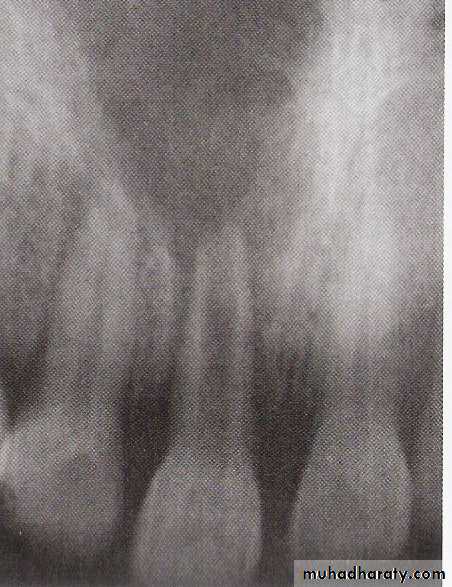

Radiographic picture: Mostly normal or mild widening of periodontal ligament.

Radiographically usually there is apical widening or radiolucency

It depend on amount of compact bone loss, not cancellous type.26